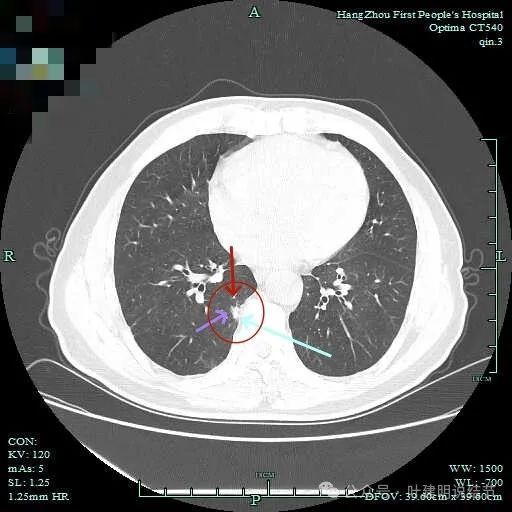

右下脊柱旁怎么也像有磨玻璃结节?但此处正常CT也是略显有慢性炎似的征象的,可这个病人明显结节状,还表面有细毛刺似的。

次病灶连续层面观察:

紧贴脊柱处混合密度,趴在脊柱上,这不像结节状。

但有小血管似的,磨玻璃部分界限较清。但此类异常影像在正常人的CT上也挺常见。

密度较高,确实像血管进入。但病灶片状,趴在脊柱上。

此层显得更呈小片状了。

与脊柱间似乎有间隙在,另见微小血管进入这条索状的偏高密度影处。